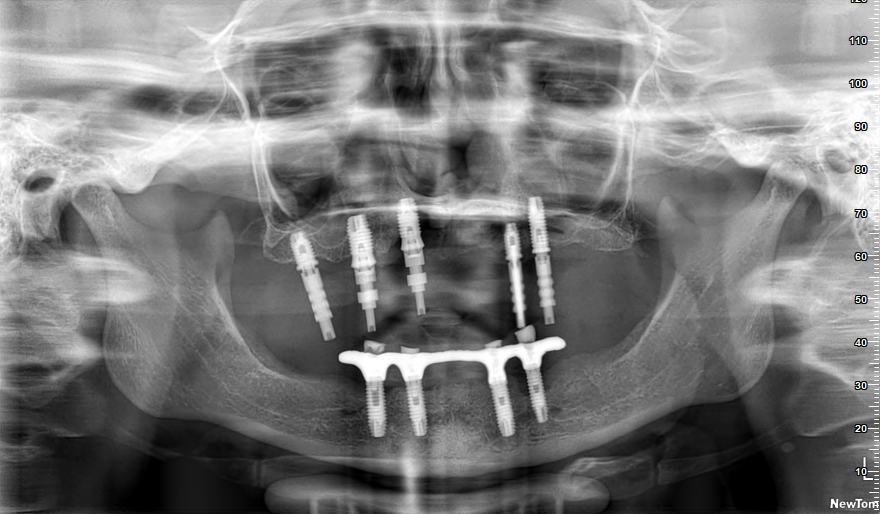

A paciente fraturou a protese superior e precisa de reabilitar com uma nova. Já pedimos ajuda a vários tecnicos e especialistas, para identificar os implantes mas só conseguimos solução de [...]